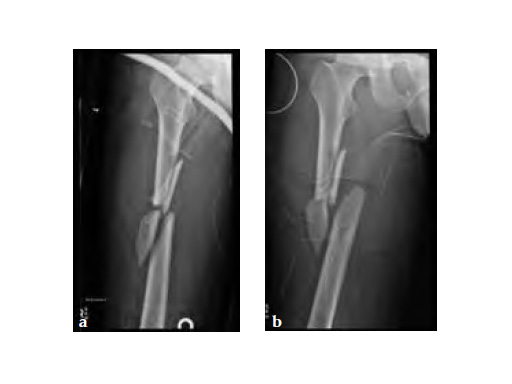

After initial stabilization with an external fixator, the femur was nailed in a closed fashion stabilized with an AFN2 in static mode. The accurate length of the injured femur was contemplated from the uninjured leg.

9-month follow-up demonstrates that that the fracture is uniting.